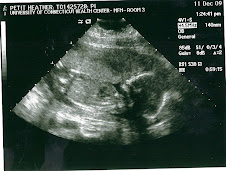

Yay! We are super excited! Today was the Level 2 ultrasound up at UConn and everything went really well. All the tests and blood work came back good and no signs at all of any birth defects (i.e. down syndrome, etc.) God rocks! Make sure to check out the new pics of Sydney we got today at UConn.